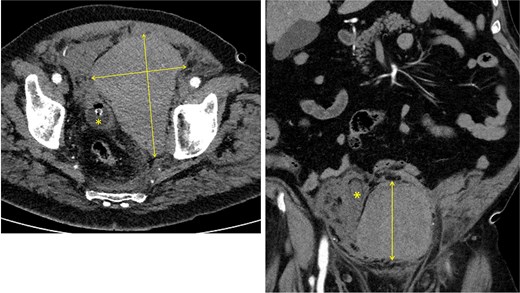

Approximately 6 h after biopsy, the patient was admitted to the emergency department with deterioration, abdominal pain, hypotension, and tachycardia. On arrival, blood pressure was 80/40 mmHg and tachycardia (124 bpm). Laboratory tests revealed leukocytosis (21.9 × 109/l), elevated creatinine (132 μmol/l, eGFR 44 ml/min/1.73 m2), and hemoglobin 6.9 mmol/l. Emergency computed tomography (CT) revealed a large left-sided extraperitoneal hematoma (14 × 11 × 9.5 cm) that displaced the bladder, with capsular venous bleeding but no major arterial source (Figs 2 and 3). Hemodynamic stabilization was achieved with fluid resuscitation and norepinephrine at 0.1 μg/kg/min. Cefotaxime was initiated empirically.

Left: axial CT showing a 14 × 9.5 cm extraperitoneal hematoma with urinary catheter balloon marked by an asterisk. Right: coronal CT showing an 11 × 9.5 cm extraperitoneal hematoma with the urinary bladder displaced to the right, indicated by an asterisk.